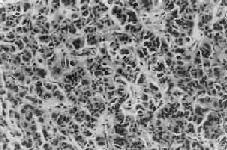

1.B细胞肿 从胰岛B细胞(即B细胞)发生的肿有腺和腺;其中一部分能分泌胰岛素,可称之为insulinoma,临床上可有低血糖症状。大约80%是单发性腺,10%为多发性腺,10%是。本可见于各个年龄层,但以40~50岁为多见。肉眼观,一般以胰体及胰尾部为多见,有完整包膜,大小为0.5~10cm,切面色微黄。组织学上,细胞似胰岛细胞,呈多角形或柱状,胞浆颗粒状,细胞排列成条索或巢状,有时可出现菊形团排列。周围绕以血窦(图15-19)。间质中常出现淀粉样物质或钙盐沉积。其恶性者称为胰岛细胞。但由于肿细胞常可因变性而出现多形性和奇异形核,因而从镜下区分良恶性有时也颇困难,常需根据其浸润性生长和淋巴结、肝转移等才能做出判断。

图15-19 胰岛细胞